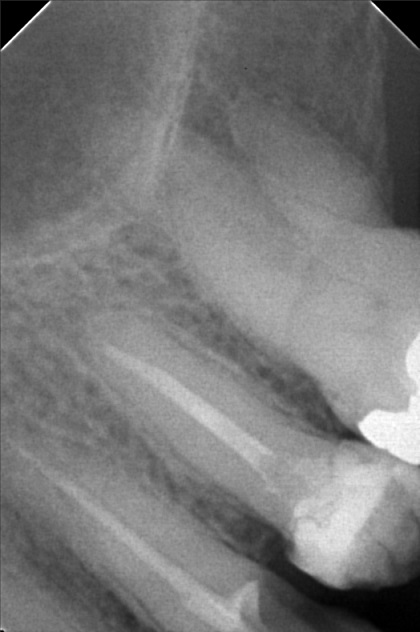

Edit Record Check our patient data records. Add patient information Patient Info Profile picture Last Name First Name Middle Name Birthdate Age Street Barangay City Country Zip Code Contact number Email Procedure > #25 buil-up w/fiber pero > 20mm obturation > xray > icf 09/03/22- open canal/ ML canal Eugenol/ Tf 9/10/10- MB #25 20mm, ML #30 20mm/ Camphenol, TF File sylvia_mariano.jpg File 2 sylvia_mariano_2.jpg File 3 sylvia_mariano_3.jpg File 4 sylvia_mariano_4.jpg File 5 File 6 File 7 File 8 File 9 File 10 File 11 File 12 File 13 File 14 File 15 File 16 File 17 File 18 File 19 File 20 Retain Record Retain Record Yes No Save Your Changes